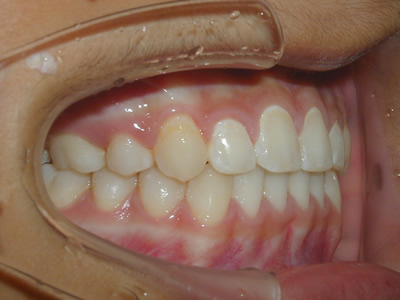

上顎の劣成長 (成長不足) による反対咬合で、上顎は拡大装置と上顎前方牽引装置を併用し前方方向への成長を促して前歯の咬み合わせを改善した後に、上下顎の前歯をマルチブラケット装置で並べました。治療の期間は2年でした。

1期治療終了時